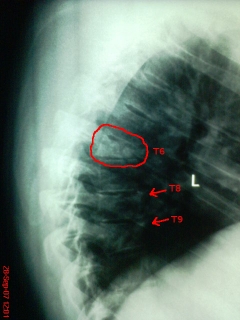

I had a follow-up appointment with the doc today after the accident where I broke my back in 3 places 9.5 weeks ago.

T6 was shattered, T8 and T9 just had fractures.

So here 'tis - this is was a vertebrae looks like after going for a dive over a bonnet and landed square on your head...

Mate, you're lucky you can still walk :shock:. Did they fuse the T6 and T7 together, I can't see any remnant of the disc left...